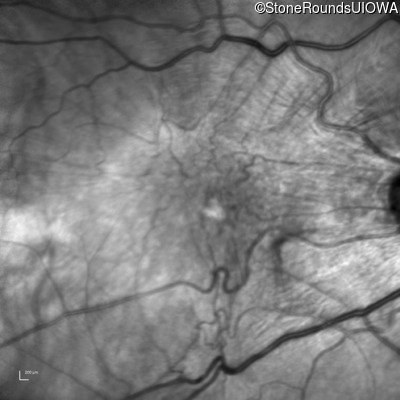

Infrared Fundus Photograph - Right - 20/200 sc

Exemplar